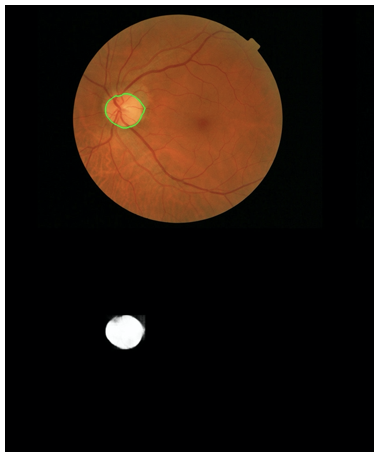

(A) 眼底彩照,绿框为黄斑区域;(B-D)不同深度的OCTA图像。